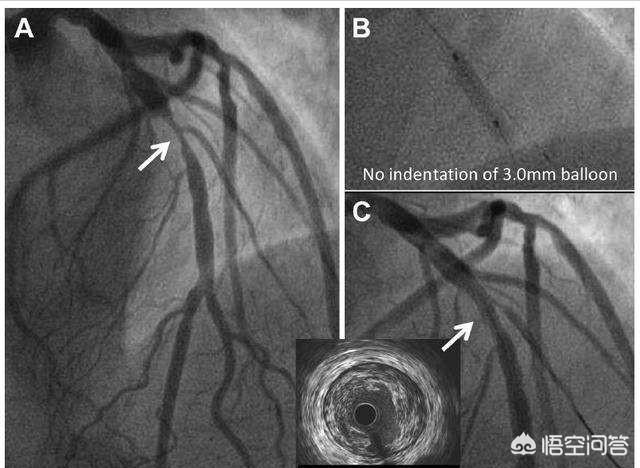

6. coronarographie (coronarographie transartérielle percutanée)La procédure. Elle consiste en une ponction artérielle (artère radiale au poignet ou artère fémorale à la base de la cuisse) pour amener un cathéter jusqu'à l'orifice de l'artère coronaire, injecter un produit de contraste iodé pour observer la morphologie de l'artère coronaire et le flux sanguin, et diagnostiquer généralement une maladie coronaire avec une sténose de plus de 50 %. Cette méthode est actuellement "l'étalon-or" pour le diagnostic de la maladie coronarienne. Elle a l'avantage d'être précise (bien sûr, il existe des cas d'imprécision, dus à l'angle de projection, à l'expérience du médecin, à la déformation du vaisseau, etc.), et de pouvoir être traitée immédiatement après la détection du problème, en utilisant la dilatation par ballonnet ou le stenting (et d'autres techniques) pour ouvrir l'artère coronaire et améliorer l'apport sanguin, et pour détecter et traiter le problème dans le même temps. Cette méthode est une procédure peu invasive dont la technologie a fait ses preuves et dont la sécurité est excellente. Mais comme il s'agit d'une procédure, il y a des blessures, des risques et le même problème avec les produits de contraste.

- La coronarographie est une technique de pointe en matière de plomberie.Le principe de la coronarographie est similaire à celui de l'angiographie coronaire, mais la coronarographie est un examen invasif au cours duquel un tube est envoyé par une artère de la main ou de la cuisse jusqu'aux artères coronaires du cœur, où un agent de contraste est injecté directement dans les artères coronaires, et la morphologie des artères coronaires est visualisée sur une caméra de film (DSA).Ce test est l'étalon-or pour le diagnostic de la maladie coronarienne, et il est capable de voir non seulement le tronc principal et les grandes branches des artères coronaires, mais aussi certaines des branches plus petites. On dit qu'il s'agit d'un plombier avancé, surtout parce qu'il peut être utilisé non seulement pour diagnostiquer la maladie coronarienne, mais aussi pour délivrer des ballons ou des stents, etc. à travers ce cathéter en vue d'un traitement, ce qui est connu sous le nom de thérapie interventionnelle coronarienne.

coronarographie

La coronarographie reste l'examen de référence pour le diagnostic clinique de la maladie coronarienne, mais elle présente l'inconvénient de nécessiter l'utilisation de produits de contraste et de procédures interventionnelles invasives. Pour évaluer le degré de sténose des artères coronaires, la coronarographie peut évaluer les changements fonctionnels des artères coronaires, y compris le spasme des artères coronaires et la présence ou l'absence de circulation collatérale ; en même temps, elle peut également prendre en compte l'évaluation de la fonction du cœur gauche et ainsi de suite. S'il est confirmé qu'un stent peut être placé dans la zone infarcie pour reconstruire le flux sanguin, un stent doit être implanté directement pour ouvrir le flux sanguin dès que possible, afin de minimiser les dommages myocardiques provoqués par l'infarctus aigu.

Pour la plupart des patients soupçonnés d'être atteints d'une maladie coronarienne grave, les médecins recommanderont une coronarographie afin d'évaluer en détail le degré de sténose de l'artère coronaire et, sur cette base, la maladie coronarienne peut être traitée directement par des techniques de pose d'endoprothèses coronariennes.

4. la coronarographie : c'est l'"étalon-or" pour le diagnostic de la maladie coronarienne. Elle permet de déterminer si les artères coronaires sont rétrécies ou non, le degré, l'étendue et la localisation du rétrécissement, etc. et d'orienter les mesures à prendre pour le traitement. Parallèlement, la ventriculographie gauche permet d'évaluer la fonction cardiaque.

5. échographie et échographie intravasculaire : l'échographie cardiaque permet d'examiner le mouvement de la paroi ventriculaire du cœur, la fonction et la morphologie du ventricule gauche, et cette méthode est l'un des moyens d'examen les plus couramment utilisés à l'heure actuelle. Elle a une valeur diagnostique importante pour la fonction du muscle papillaire, la rupture cardiaque, le thrombus intracavitaire et la tumeur de la paroi ventriculaire. L'échographie intravasculaire peut clarifier le degré de sténose et la morphologie de la paroi des artères coronaires, ce qui constitue une nouvelle technologie prometteuse.